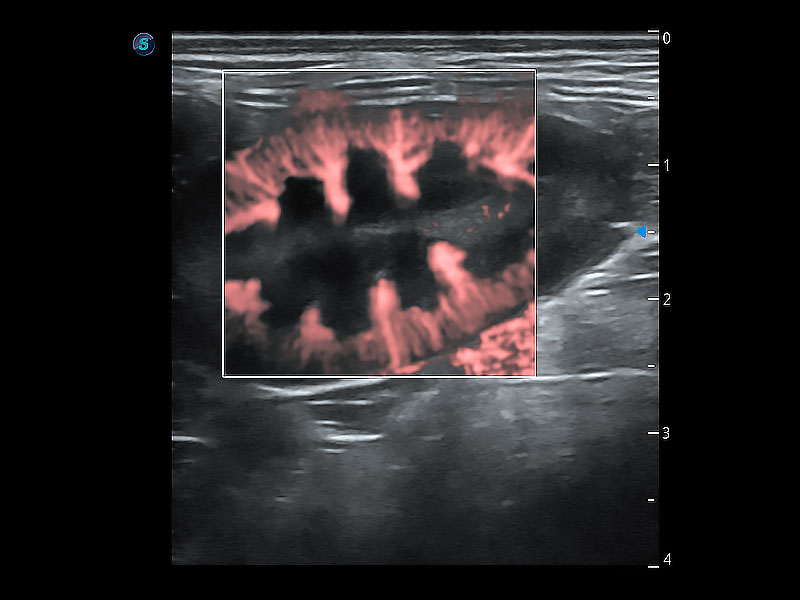

(犬)肾脏显微血流

• Micro F 显微血流成像

极大提升超低速微细血流的检出能力,同时更精准地滤除软组织和超声信号,为兽用医生提供以往无法通过常规血流获得的疾病诊断信息。